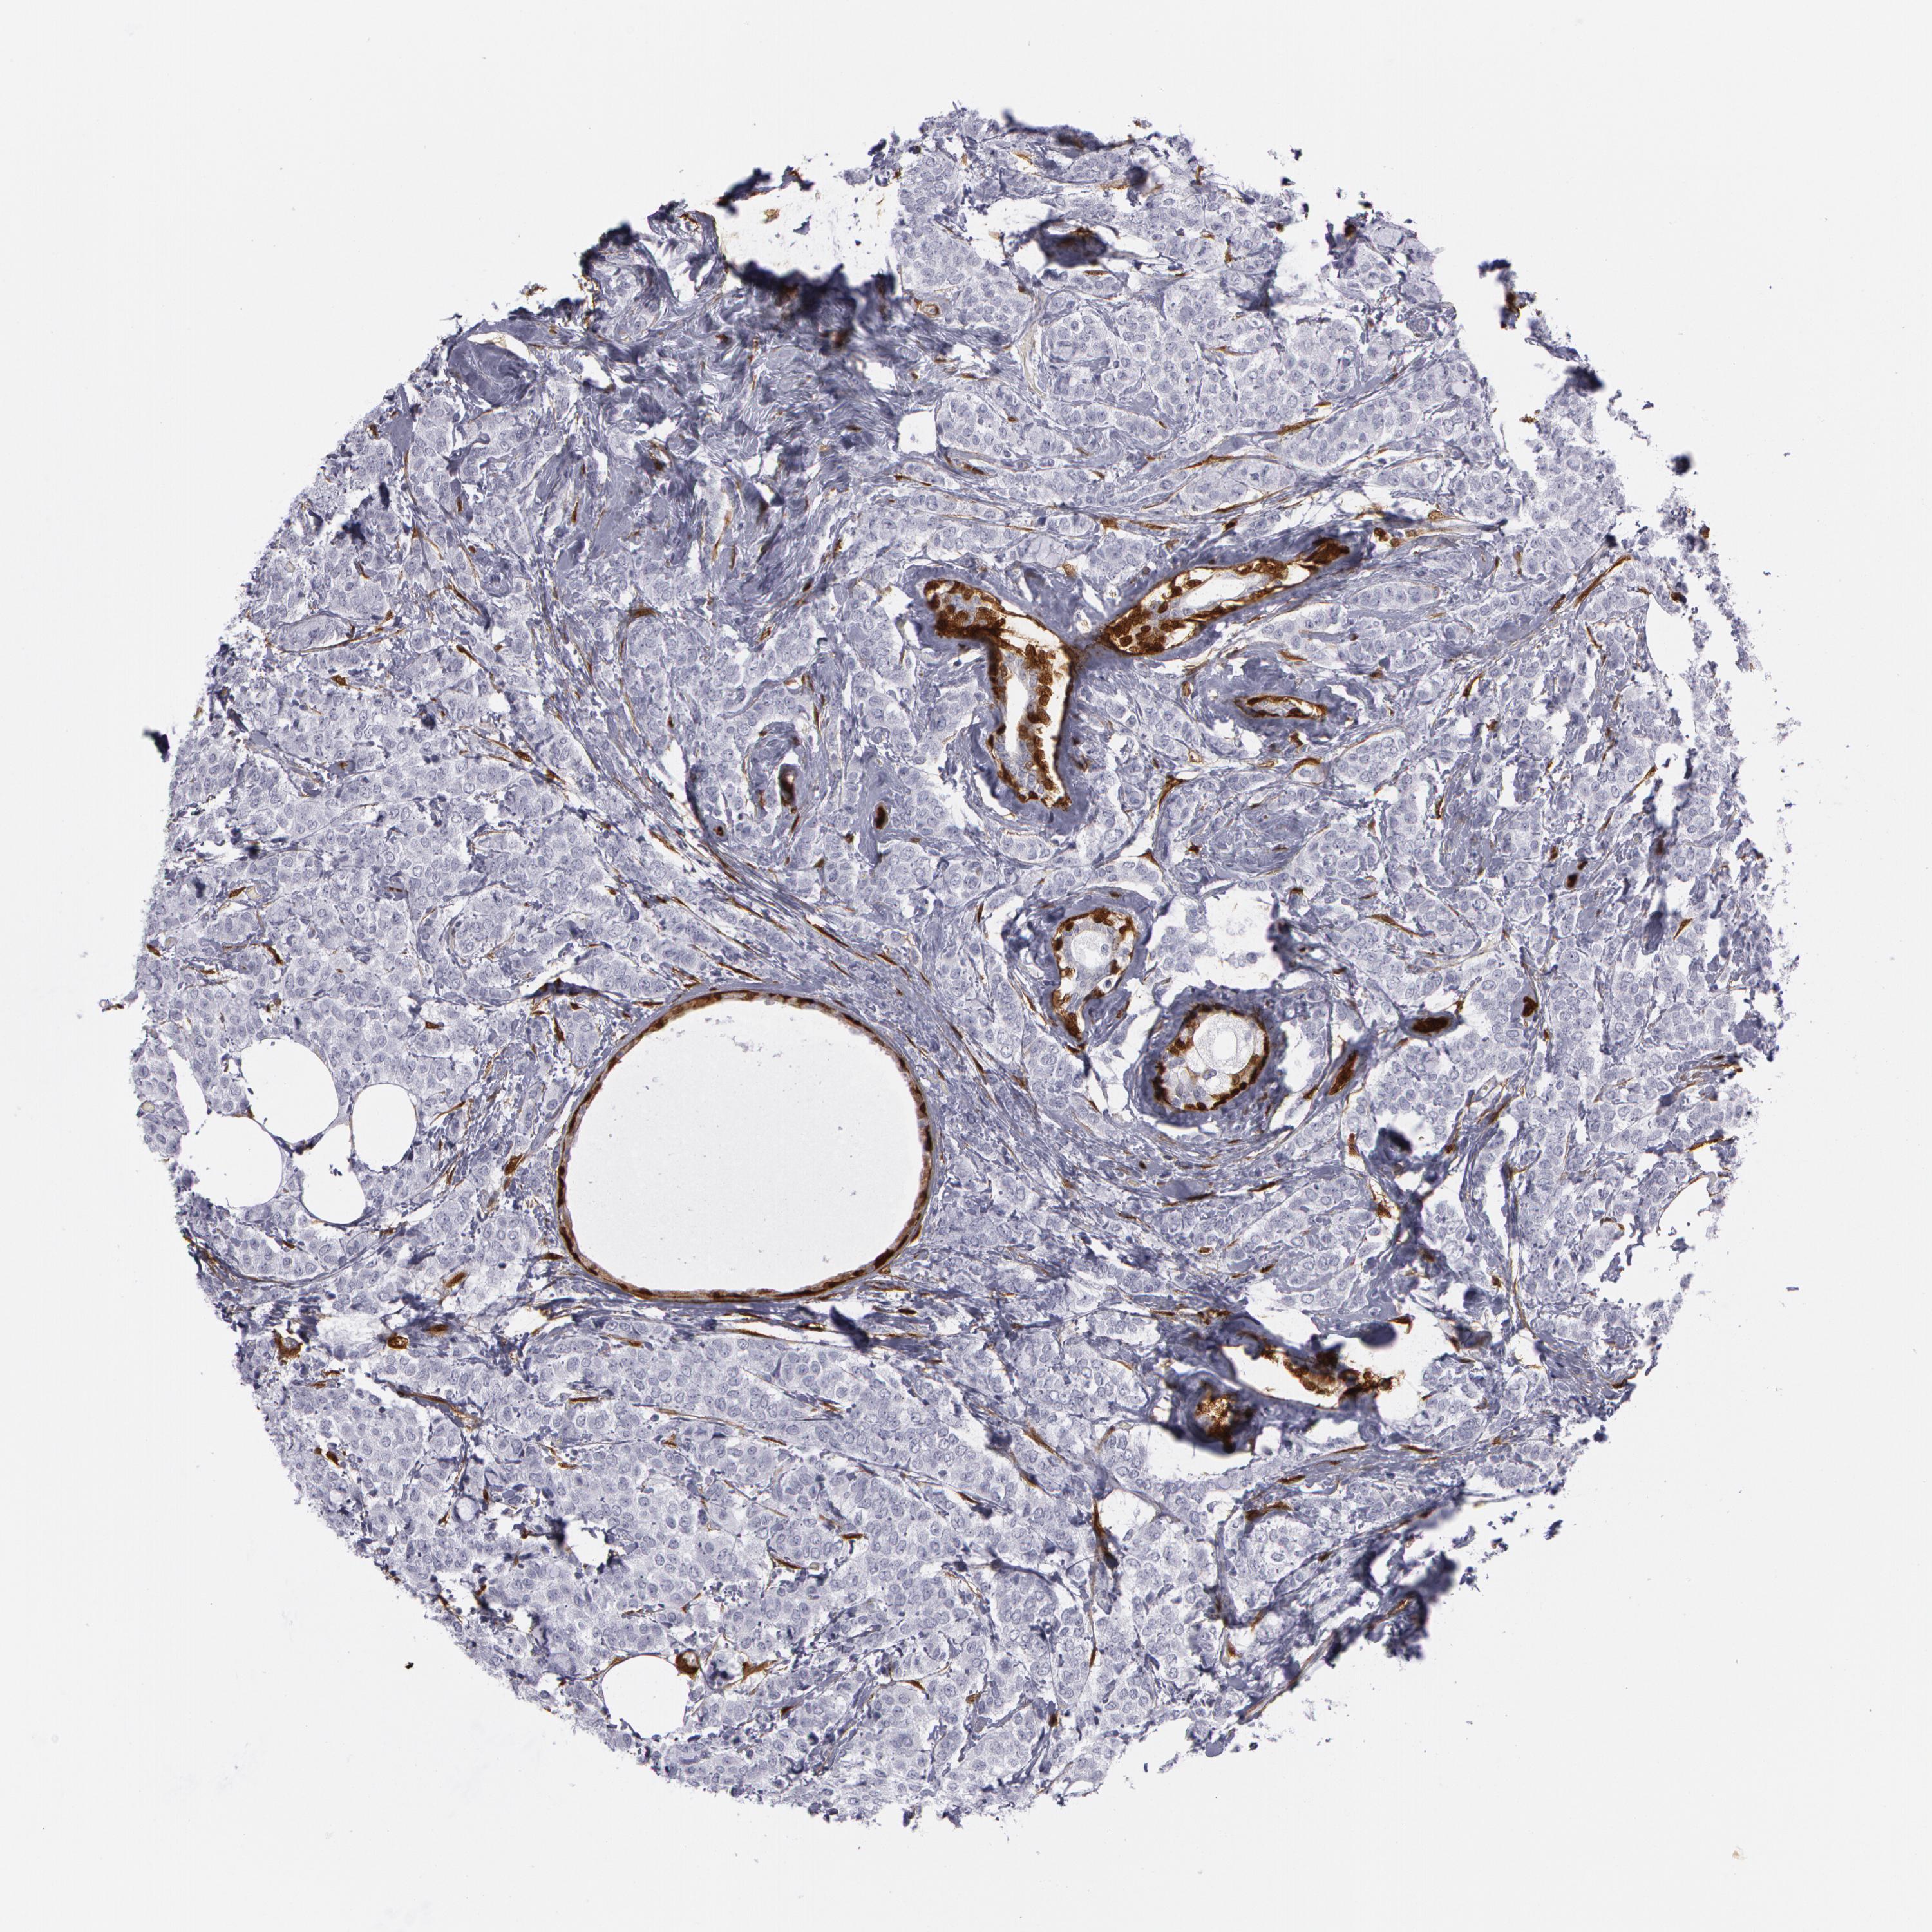

BRCA TCGA BRCA VALIDATION PROTEIN EXPRESSION